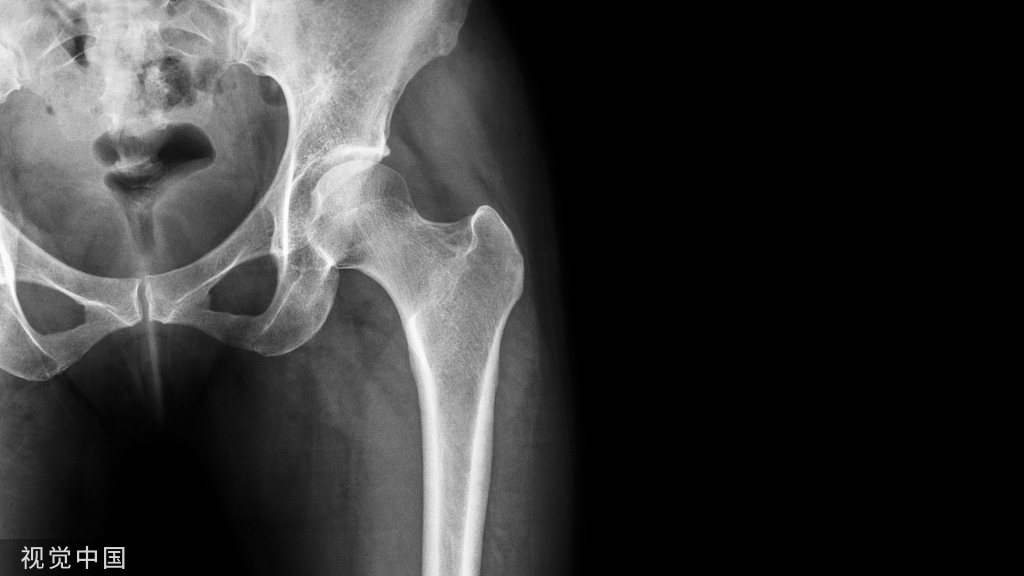

12、股骨大粗隆:股骨大小粗隆骨骺一般在15-20岁愈合。